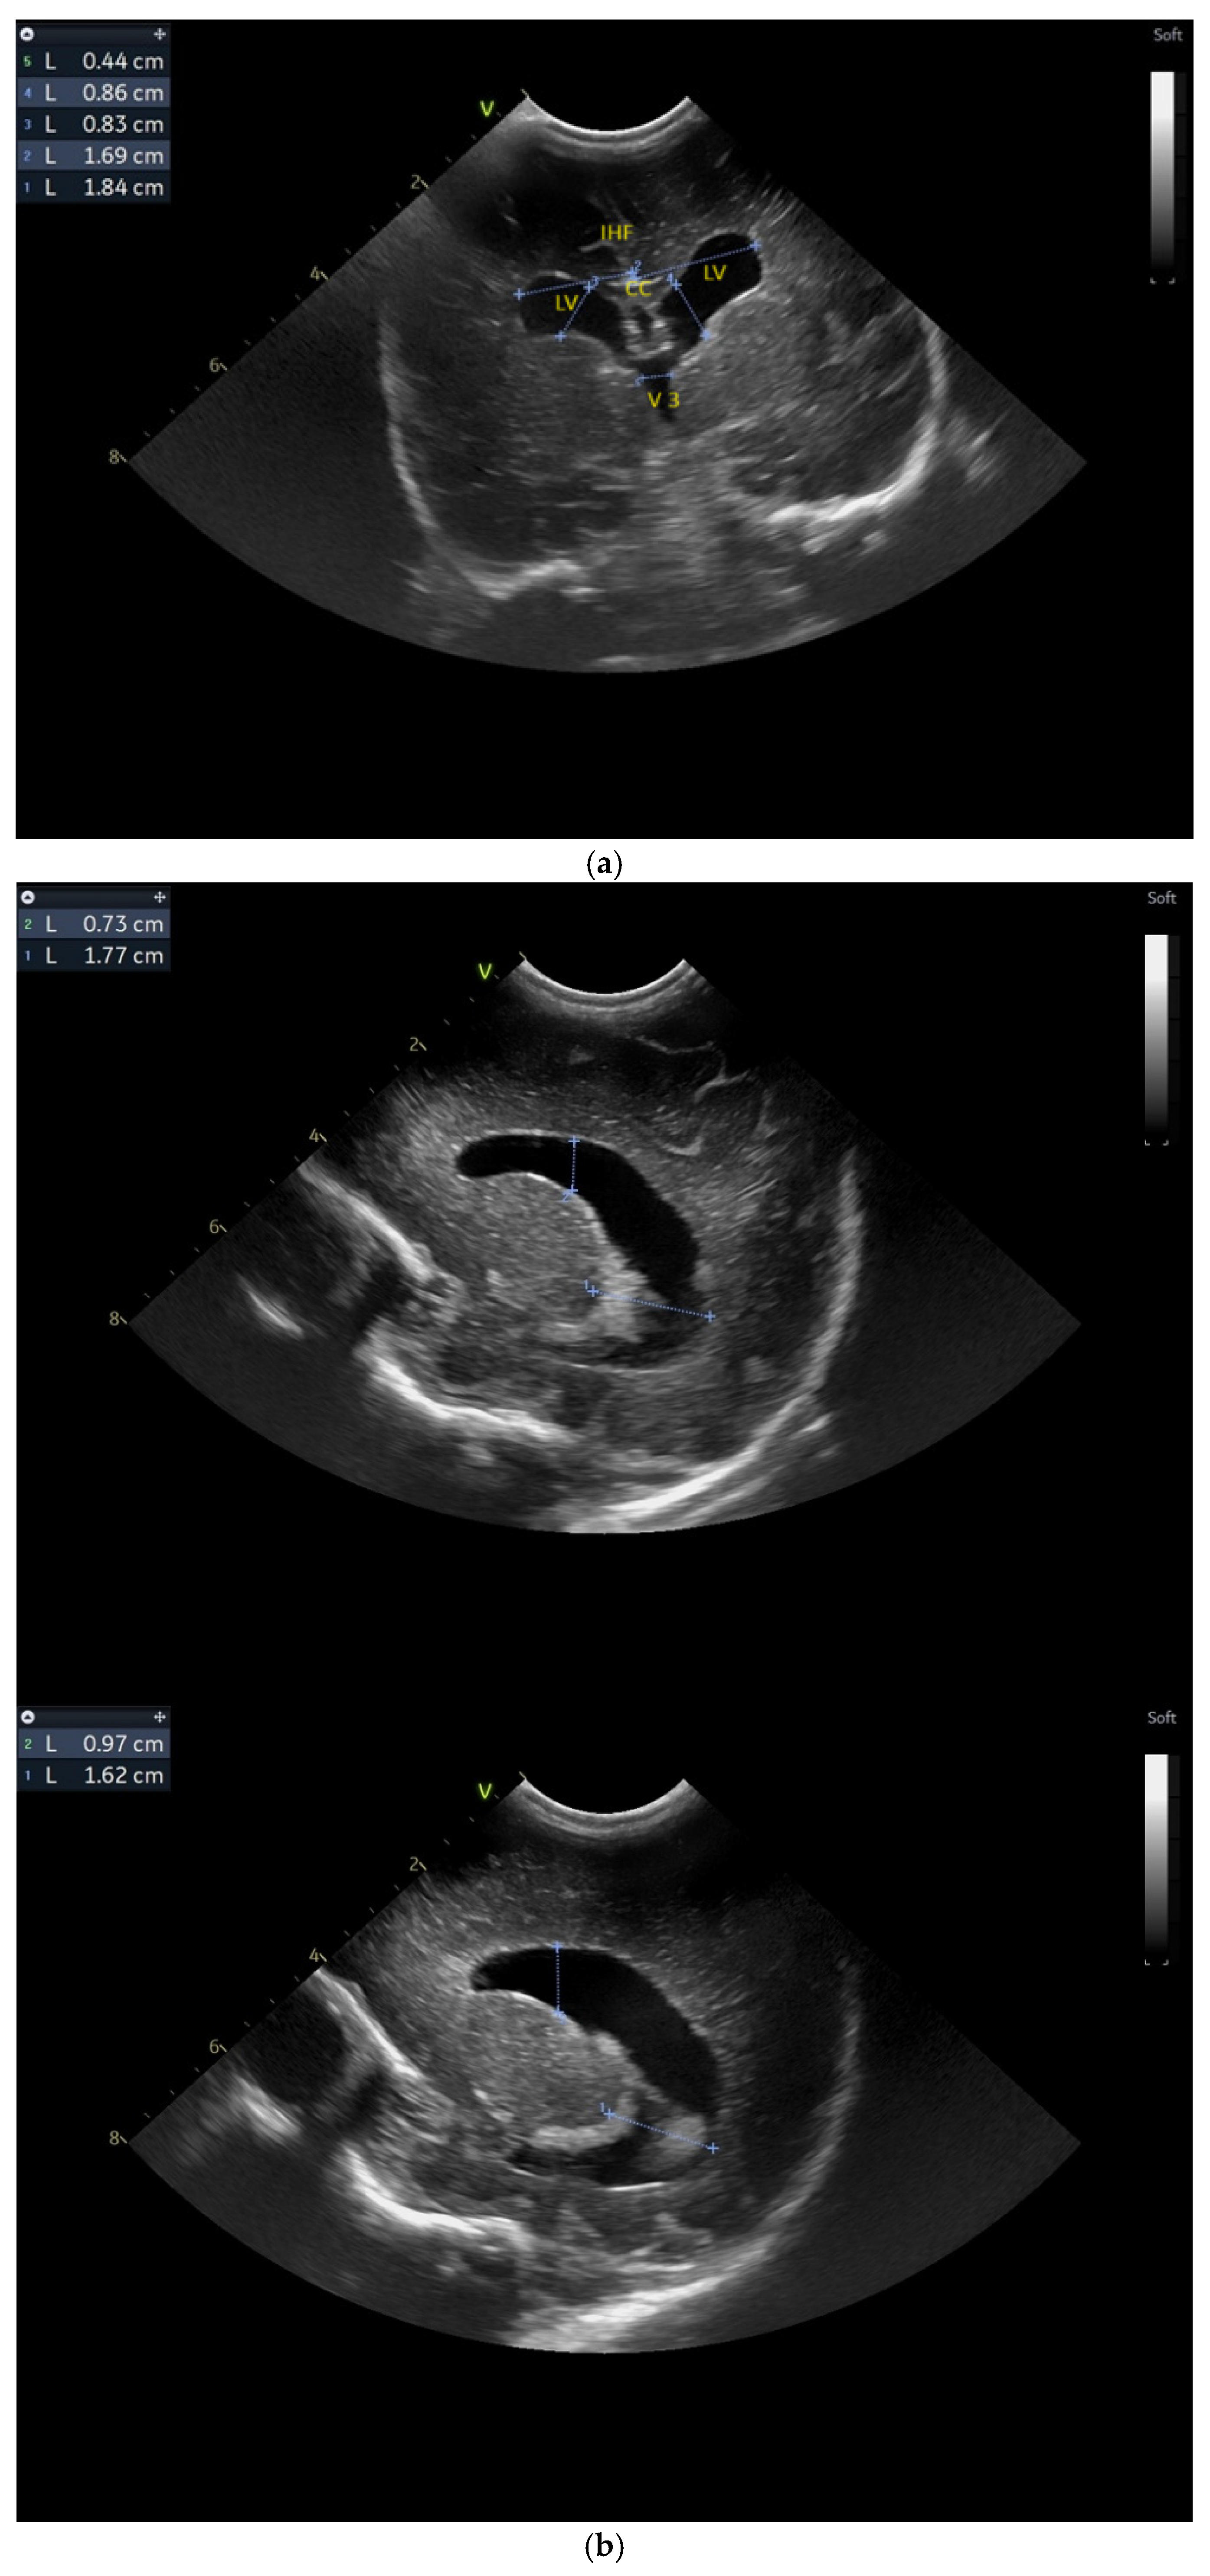

(a) Cranial ultrasound. Coronal view. Lateral ventricles and third ventricle enlargement. L1, L2—Levine index measurement. L3, L4—posterior horn of the lateral ventricles’ width measurement. L5—third ventricle width measurement (personal image collection). (b) Cranial ultrasound. Sagittal view. Enlarged third and fourth ventricles. L1, L2—third ventricle measurements. L3, L4—fourth ventricle measurements (personal image collection). (c) Cranial ultrasound. Sagittal view. Enlarged lateral ventricles. Up—left ventricle. Down—right ventricle (personal image collection). (d) Cranial ultrasound. Coronal view. Punctuate hyperechoic images were observed in the right lobe (personal image collection). (e). Up left—MRI T1 sequence. Up right—MRI T2 sequence—susceptibility weight imaging (SWI). Down—CT scan. Transversal view. Yellow arrows—multiple calcifications can be seen in the CT scan (personal image collection). (f) Cranial ultrasound. Coronal view. Lateral ventricles. L1, L2—Levine index measurement. L3, L4—anterior horn width measurement. Blue arrow—intraventricular shunt (personal image collection). (g) Cranial ultrasound. Sagittal view. Thalamo-occipital distance measurements. Up—right ventricle. Down—left ventricle (personal image collection).

At six weeks after birth, an MRI scan was performed, while a CT scan was performed at 14 weeks of life, both providing valuable information regarding the sequelae of Toxoplasmosis (Figure 4e). Even though a few signs were observed on the MRI, the CT scan better outlined the presence of the parenchymal calcifications. A neurosurgical intervention was intended, a ventricle puncture was performed, and a shunt was placed in the right ventricle. The cranial ultrasound at two months of life did not show notable improvements, however (Figure 4f,g). The neurological examinations showed axial hypotonia and limb hypertonia.

Five weeks after birth, the patient presented for the first cranial ultrasound examination, which revealed enlarged ventricles and the presence of a hyperechoic image in the right frontal lobe, suggestive of calcifications. The parenchymal tissue was reduced (Figure 4a–d). The anterior fontanelle was wide, with large sutures. The neurological assessment showed that the infant could keep eye contact and would also hold its head during the traction-to-sit maneuver but was not able to lift its head while in the prone position. The passive tone assessment showed the “scarf sign”, with the elbow at the midline and a popliteal angle range for both legs of 90–100°. Deep tendon reflexes were present. The general movement (GM) assessment revealed a poor repertoire pattern with minimal mobility in the lower limbs. Treatment for Toxoplasma was initiated.